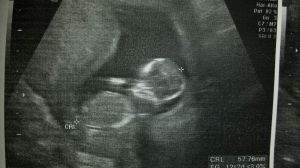

Llama al teléfono 24 horas. Insiste varias veces. Una voz de chica muy joven, dice que llama por su amiga. Es menor de edad, española, embarazada de pocos meses. El médico le ha dicho que es mejor que aborte, que fuma una cajetilla y media. Los padres la quitan el móvil, no la dejan salir de su casa. Consiguen rápidamente cita para abortar en un centro privado concertado por la Seguridad Social para hacerse el aborto. La chica está desesperada. Quiere tener a su hijo. Su mejor amiga nos llama a ver en que podemos ayudarla. Los padres le han prometido regalarle de todo si aborta, incluso un perrito.

Solo le quedan unas horas para entrar en el abortorio. No consigue que sus padres hablen con nosotros. Ya no sale de su habitación. No deja de llorar. Su hijo ya tiene un nombre. Lo lleva muy dentro de su corazón. Marta Velarde, +Futuro.